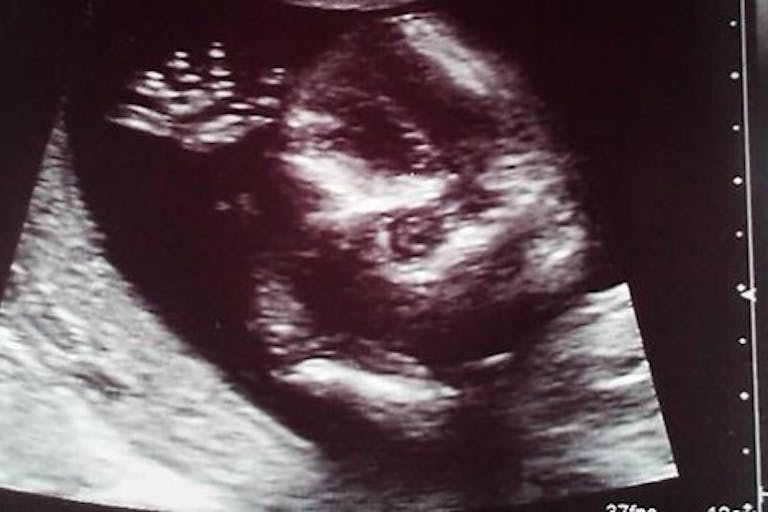

Pro-choice groups often say that pro-lifers give inaccurate information to abortion-minded women. But it is undeniable that ultrasounds show the truth. They are simply pictures. They show the baby who is there without embellishment or exaggeration. They show what is in the woman’s womb – no more, no less. Ultrasounds, by their very nature, can’t lie.

Is it better for a woman to abort, thinking she is getting rid of a few cells or a shapeless mass only to discover that her baby was fully formed, or is it better for her to know the facts beforehand? The facility may try to prevent her from seeing the image, but they won’t be there to censor abortion information from her for the rest of her life. It is likely that she will eventually learn facts about fetal development and the appearance of a preborn baby.

Is seeing an ultrasound of one’s baby a form of torture? It’s true that seeing a picture of the baby she is carrying might make abortion harder for a woman to rationalize. The sight of her baby may indeed invoke strong emotions. An ultrasound would reveal what’s at stake in her decision. It may be more difficult for her to abort after she has seen the features of her child.